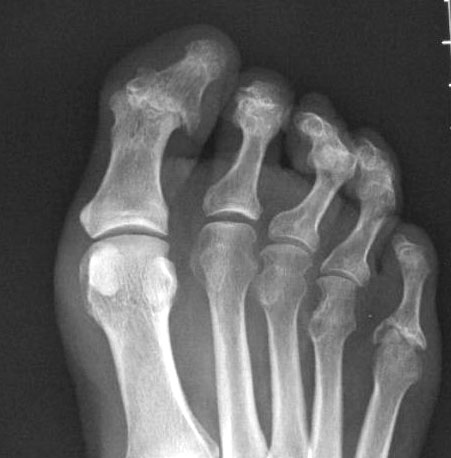

Artritis psoriásica y falange bífida.

Artritis psoriásica.